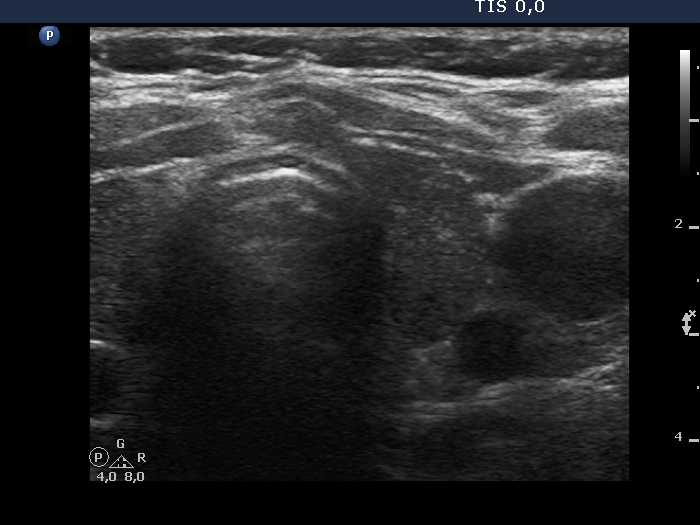

Examination in 2013 (first row of images):

Clinical data. A 50-year-old woman was referred for evaluation of a nodular goiter. The patient has been treated for hypothyroidism for 16 years.

Palpation: Both lobes were a bit firm, no nodule was palpable.

Laboratory test: TSH 4.01 mIU/L on daily 100 microgram levothyroxine.

Ultrasonography. The thyroid was minimally/moderately hypoechoic and had several discrete minimally/moderately hypoechoic lesions.

Cytology was performed from the lesion in the central part of the right lobe and resulted in Hashimoto's thyroiditis.